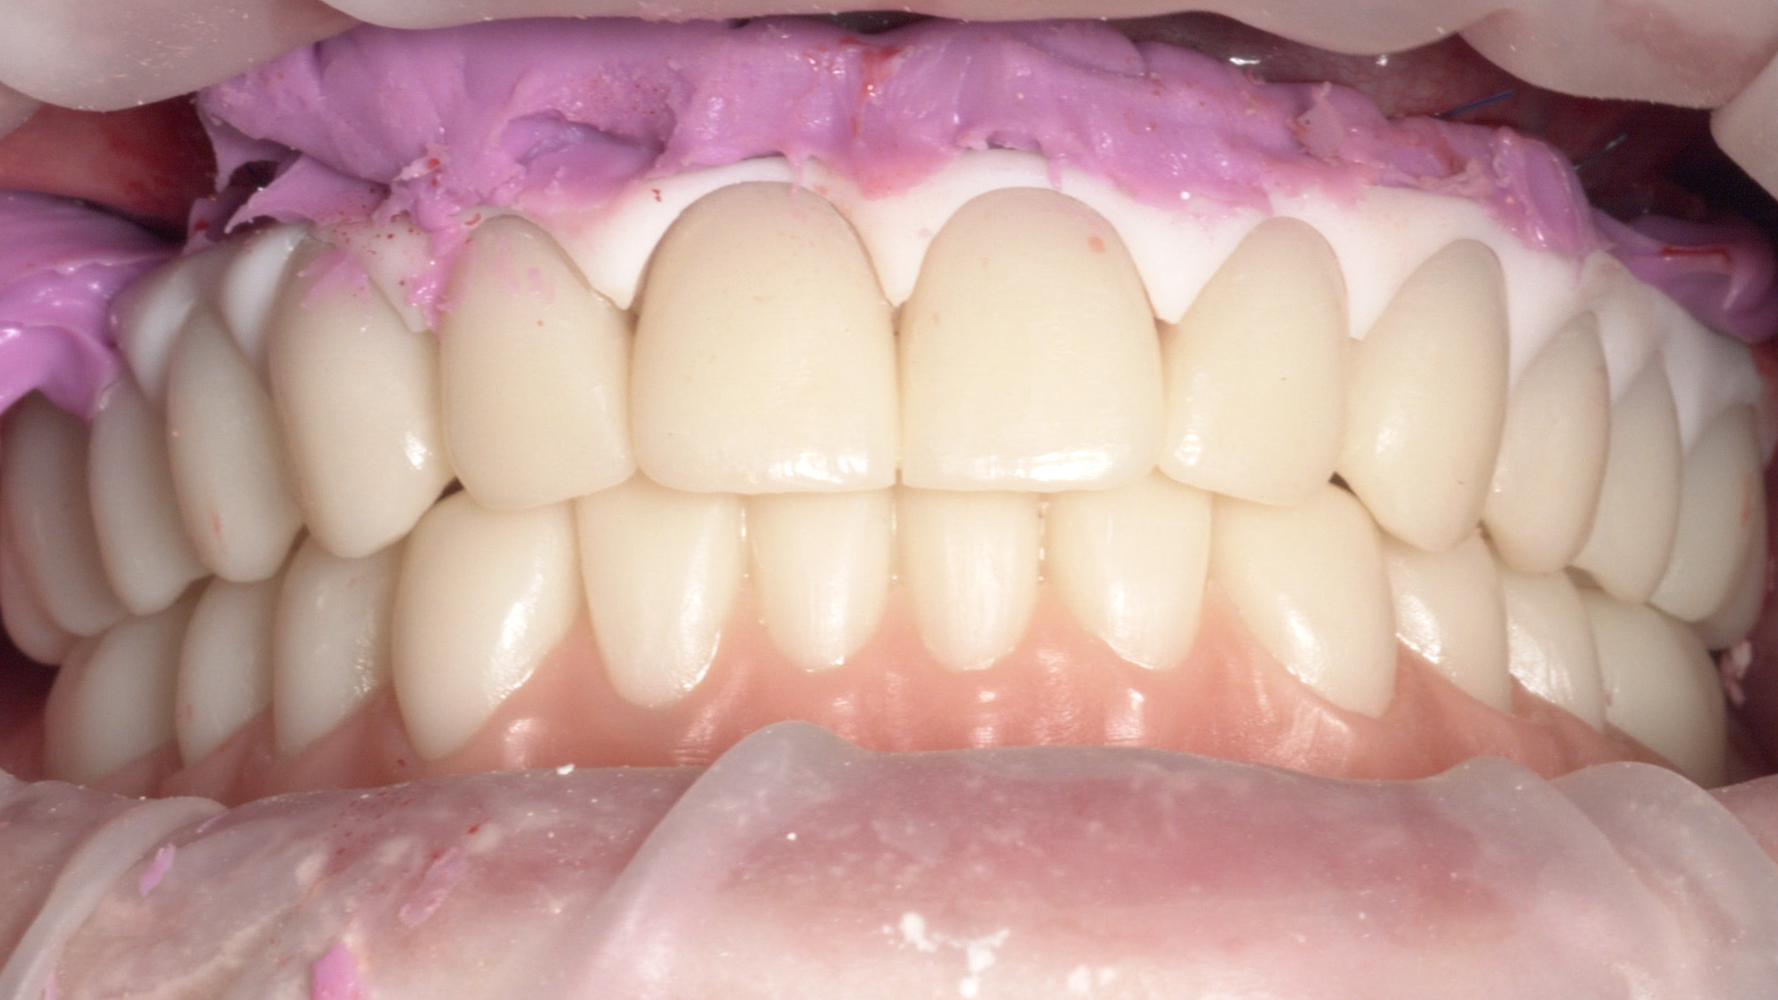

Fig. 17. Adattamento intraorale della protesi fissa provvisoria superiore e della protesi provvisoria mobile inferiore

Fig. 18. Adattamento intraorale di entrambe le protesi provvisorie fisse